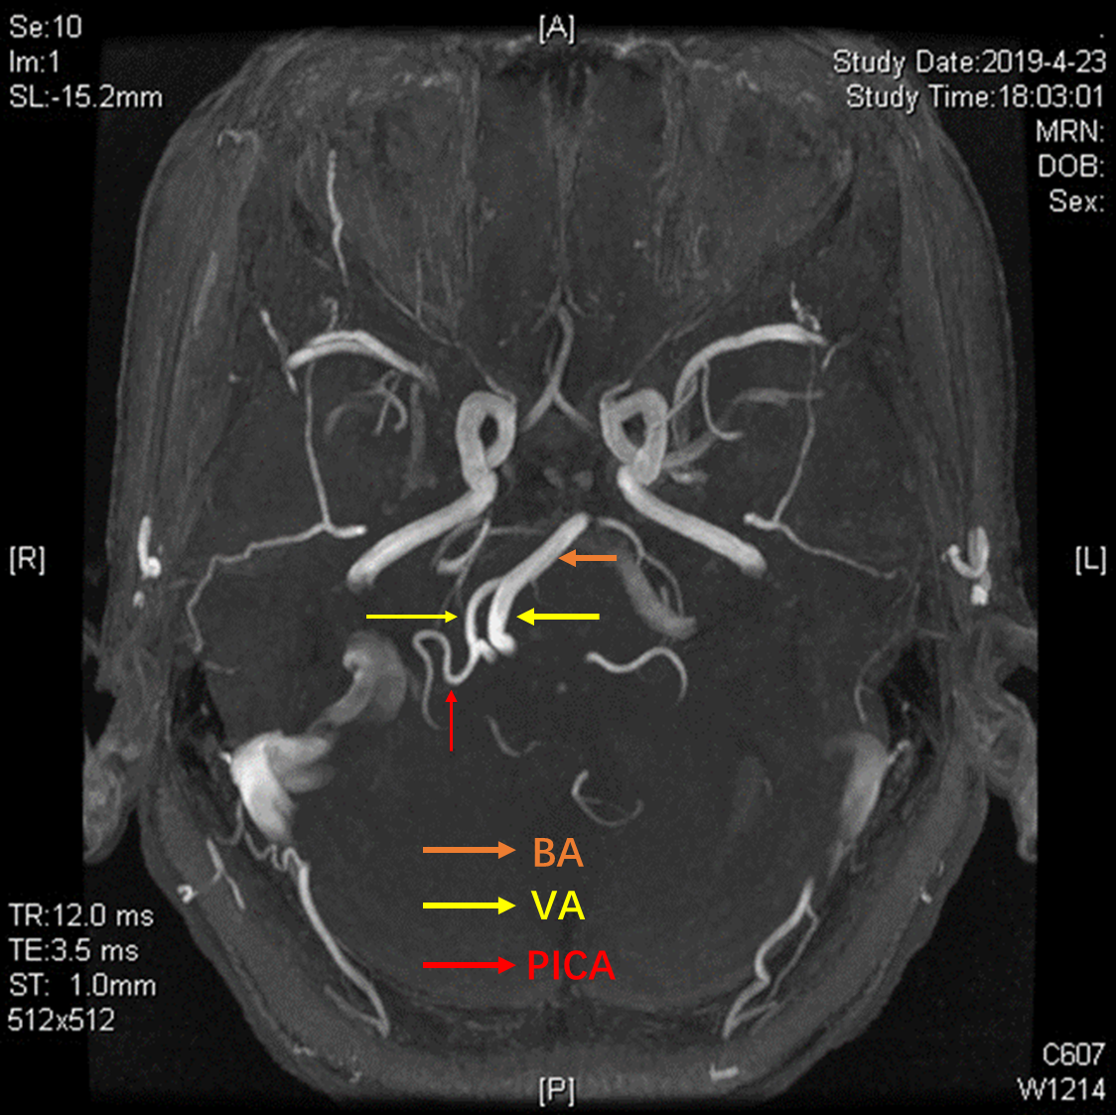

3D-TOF序列提示椎基底动脉迂曲,偏向右侧,小脑后下动脉PICA从劣势椎动脉发出,于上下各成一袢,最后绕回下方,呈“S”型。

TOF序列及FIESTA序列可见PICA在下方的第一个弯曲与面听神经关系密切。